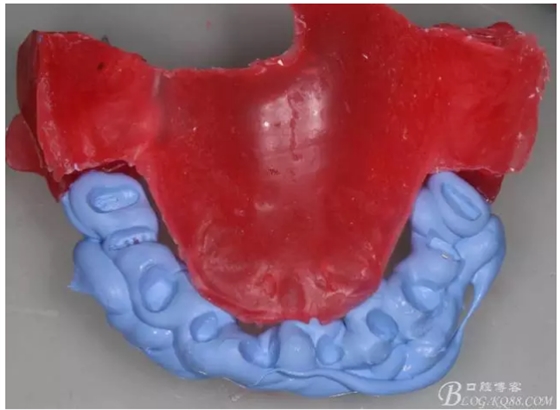

牙體預(yù)備前先咬蠟記錄,記錄患者的垂直高度,在預(yù)備后再把蠟記錄放入口內(nèi),用咬合記錄硅橡膠再記錄牙體預(yù)備后的咬合記錄

這樣就準(zhǔn)確的記錄和還原了原來的垂直高度,更多垂直距離的確定在8月3日kq88課堂上還有提及歡迎大家來聽課啊,